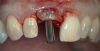

Fig 1. A female patient presented missing tooth No. 8, which would be replaced with a single implant restoration.

Figure 1

An example illustrating the manner in which these factors are considered in case selection, implant placement, and implant restoration is the case of a female patient who presented with a missing central incisor, tooth No. 8 (Figure 1 and Figure 2). While this example presents an ideal situation for a single implant-supported restoration, analysis is required to determine the appropriate implant width and length, presence of adequate bone, quality and quantity, soft-tissue health, abutment type (ie, custom or stock), and restoration type (ie, cement- or screw-retained).